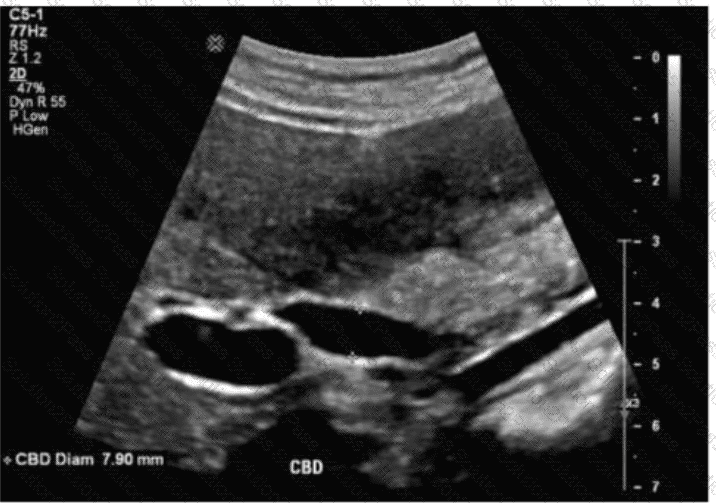

Which term best describes the common bile duct measured in this image of a postcholecystectomy patient?